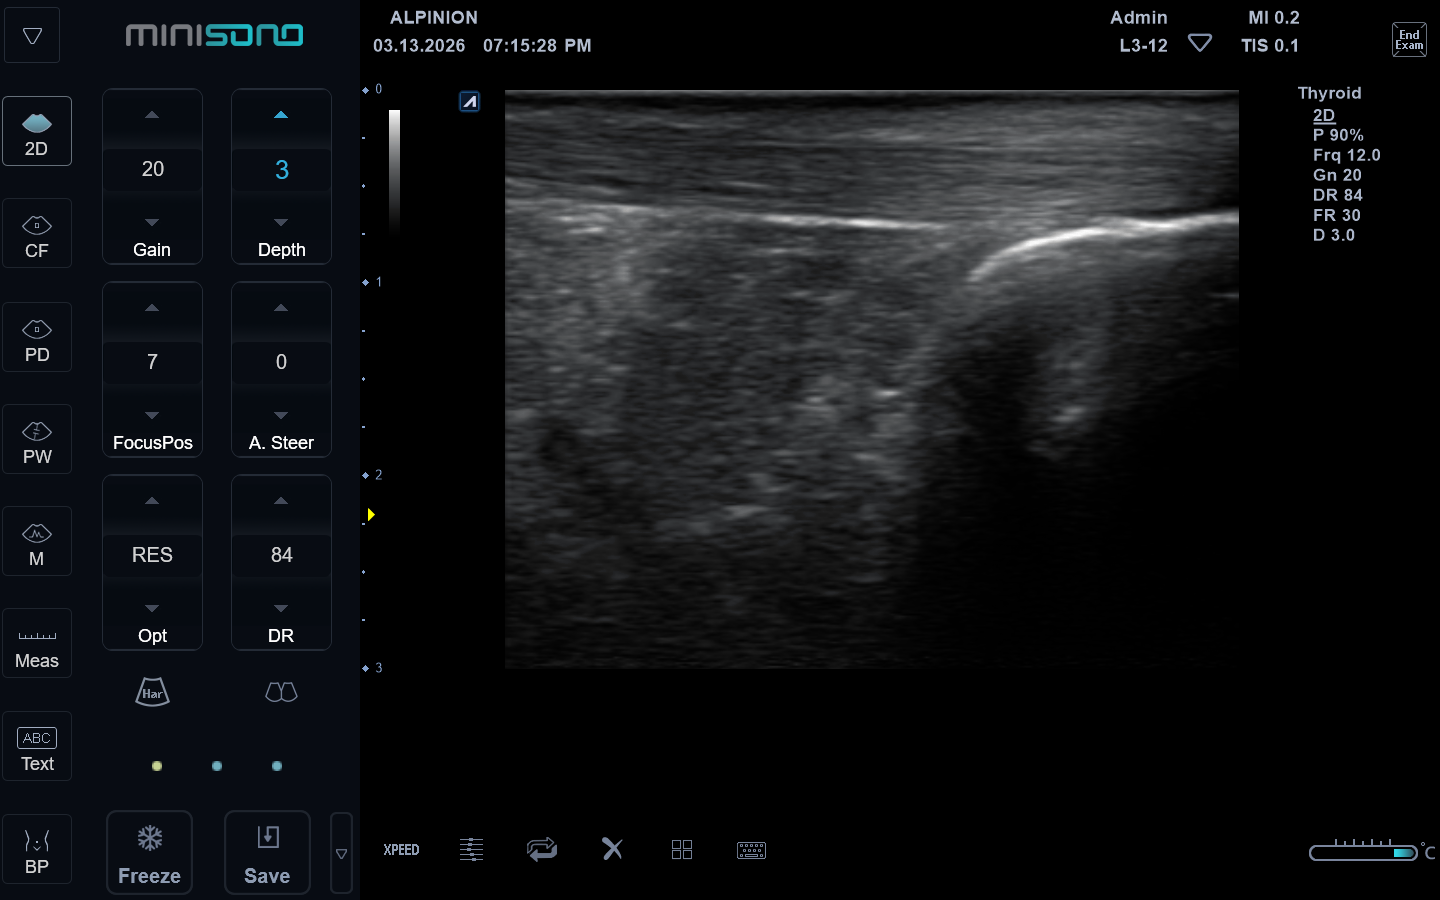

Bij klachten aan de voet of enkel is het soms belangrijk om goed te kunnen zien wat er in het lichaam gebeurt. Met echografie kunnen we spieren, pezen, banden en slijmbeurzen snel en pijnloos in beeld brengen.

Binnen Talstra Beweegt gebruik ik echografie als aanvulling op het fysiotherapeutisch en/of podologisch onderzoek. Zo krijgen we samen een duidelijker beeld van de oorzaak van de klacht en kunnen we de behandeling gerichter inzetten.

Omdat echografie dynamisch onderzoek is, kan ik ook kijken wat er gebeurt tijdens bewegen en belasten.